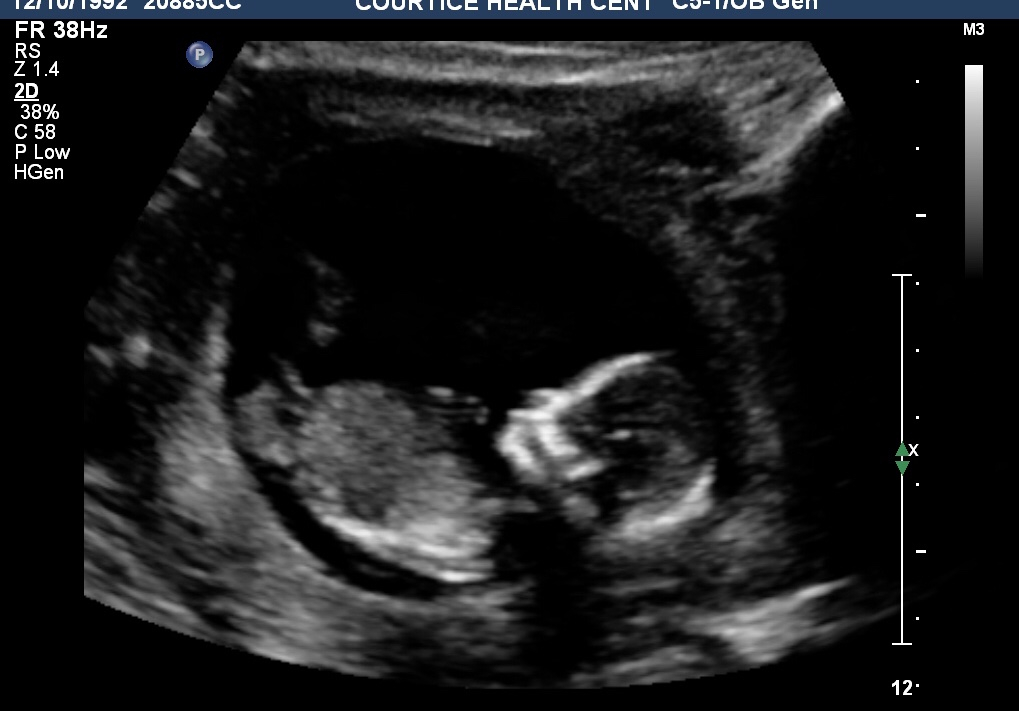

Week 10 exactly!! So cute! As soon as the doctor found the baby we saw the baby dancing and moving around! Super exciting! Due July 17,2019